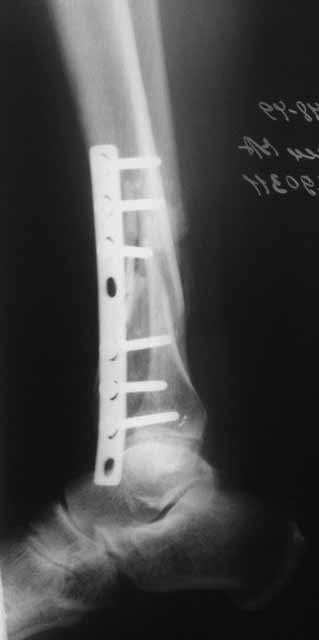

Примерная ситуация. Пациент 37 лет. Синтезировали где-то пластинкой. Попал к нам через 2 месяца.

19 апреля убрали через проколы пластину с винтами, пересекли fibula, наложили аппарат.

Немного потянули по оси, убрали вальгус, ротацию. 22 апреля (на 3-е сутки) заштифтовали окончательно. 29 апреля выписали из отделения. На все ушло 10 дней.